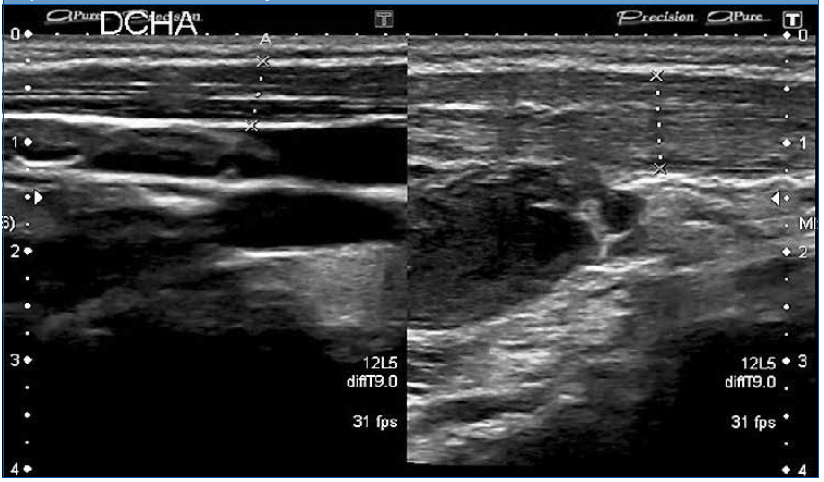

Tras una semana es revisada en consulta, persistiendo el dolor y la tumoración, esta vez indurada, sin otros síntomas acompañantes (Fig. 1), por lo que es derivada a Urgencias de su hospital de referencia, donde se le realiza una ecografía en la que se visualiza una lesión abscesificada subyacente al músculo esternocleidomastoideo (ECM), decidiéndose su ingreso para administrar tratamiento antibiótico intravenoso. Reexplorando a la paciente, se palpa el músculo ECM izquierdo engrosado en toda su extensión, por lo que se decide repetir la ecografía cervical de forma bilateral. El informe indica la presencia de un engrosamiento del músculo ECM izquierdo con respecto al derecho, con alteración de la ecogenicidad, visualizándose dos focos hipoecoicos intramusculares compatibles con piomiositis, así como la presencia de un absceso subyacente de 1,6 × 2,7 cm (Fig. 2).